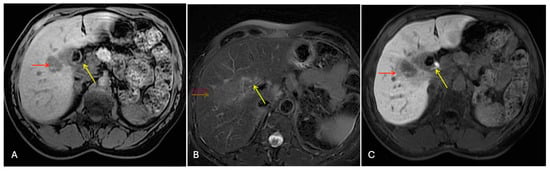

3.2.1. Case 1

3.2.2. Case 2